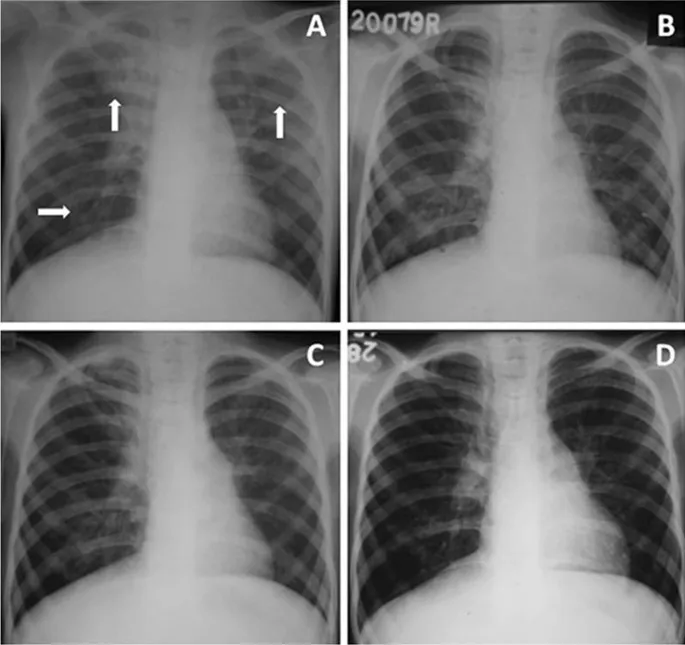

4. HIV & Thoracic Patterns Explained By Dr. Zainab Vora

In this high-yield session, Dr. Zainab Vora explains a pattern-based approach to thoracic imaging in HIV-positive patients — an essential skill for radiology residents and MD/DNB aspirants.

Learn to differentiate between:

➡️ Primary vs Reactivation TB

➡️ PCP, CMV, and Lymphoma

➡️ Ground-glass opacities, cystic lesions, and nodules

🔍 Bonus insights:

• How CD4 counts guide radiological differentials

• Real case-based HRCT and X-ray examples